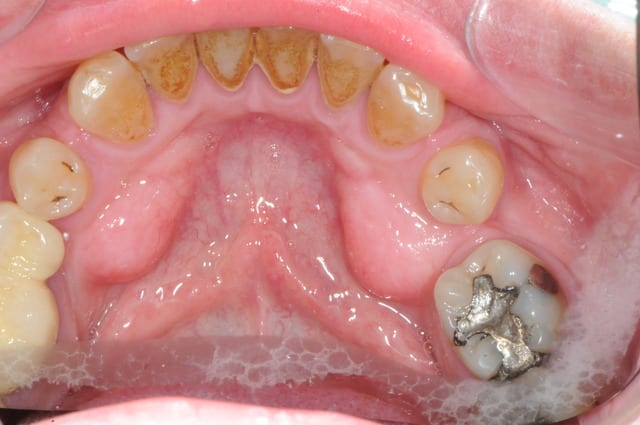

dentiste57

c'est quoi ces trucs ?

exostoses ?

Ce sont les tori mandibulaires...

apophyses géni hypertrophiées, dues à une traction musculaire importante des muscles abaisseurs...

ou alors prémolaires inférieures incluses ? a priori tori mandibulaire

ceux sont bien des tori mandibulaires, mais avec option dent incluse.